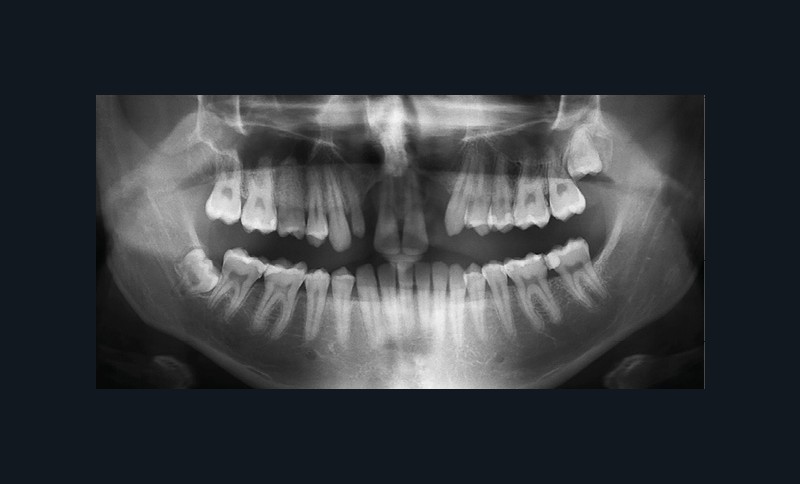

Lors de la première consultation, un examen radiographique sera nécessaire afin de s’assurer de la qualité de l’environnement osseux et parodontal si l’anamnèse ou l’examen clinique suspecte l’existence d’une fente alvéolaire à la naissance. Il s’agira toujours d’une évaluation tridimensionnelle en privilégiant un CBCT plutôt qu’un orthopantomogramme (fig. 1a, b).